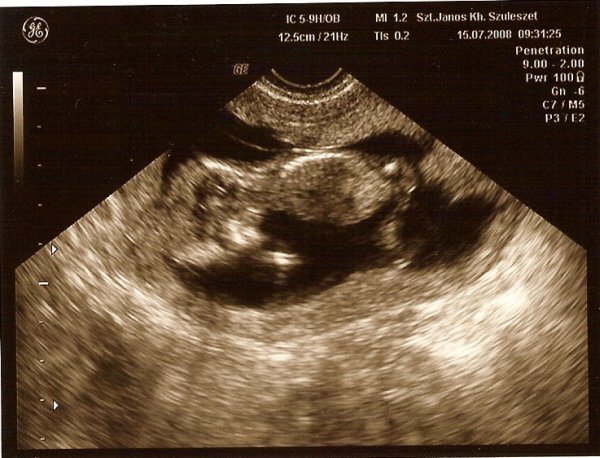

A 12 hetes UH-on Kispocok is 48 mm volt (aznap töltötte a 12 hetet), a doki normális méretűnek találta, innentől nem aggódom

, hogy 1-2 hét csúszás van-e benne... hát lehet. Holnap már 15 hetes, biztos sokat nőtt

de csak jövő héten megyünk UH-ra.